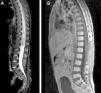

Atypical teratoid rhabdoid tumors (AT/RT) of the central nervous system are rare, very aggressive embryological tumors, typically diagnosed in young patients and having a low survival rate after diagnosis. The aim of this study was to emphasize, based on the latest results in the literature, the need for protocols for multidisciplinary treatment in these patients.

ResultsTwo of our 3 cases (supratentorial and spinal tumors) did not show any progression of the disease after long follow-up, in contrast with most of the cases available in the literature. The second patient had a shorter survival.

ConclusionsPatient age at the time of diagnosis, supratentorial location of the mass and fewer complications with adjuvant treatments seem to be factors yielding good prognosis for AT/RT tumors. In agreement with the latest international protocols, multidisciplinary treatment is the ideal treatment, consisting of radiotherapy and chemotherapy after complete tumor resection.